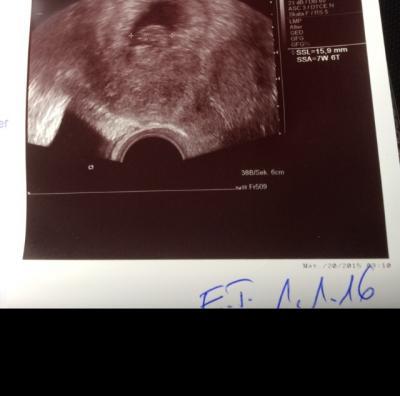

Hier zweiter offizieller FA Termin mit Herzchen Bubbern und Terminbestätigung und MuPa Übergabe (der 4. dann :))) ). Sooo und nun Puste ich dich (und alle die noch bangen/Hibbeln) an!!!

Bild zu Ganz viel Viren für mein Lieschen!!! - Forum für Januar - Mamis